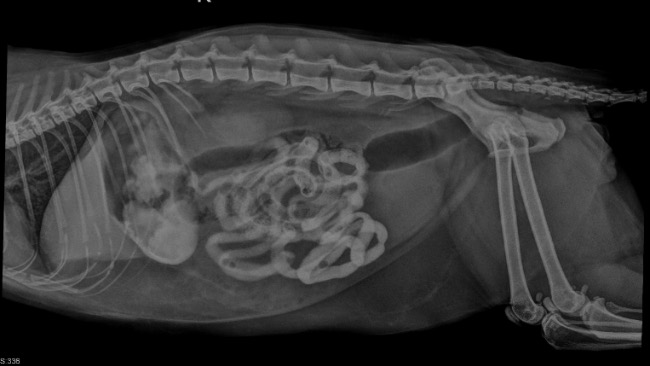

Orionek nagle poczuł się bardzo źle . Najpierw wysoka temperatura , i nagle niska. Po szybkiej diagnozie podejrzewano zapalenie otrzewnej. Dwukrotne USG, dwukrotny RTG z kontrastem nie potrafił pomóc lekarzom stwierdzić i postawić konkretnej diagnozy . Stan z godziny na godzinę był coraz gorszy ,wyniki krwi tragiczne.

Lekarze zdecydowali się na laparotomię po której usłyszeliśmy, że wnętrza -wątroba, jelita są w bardzo złym stanie - jest bardzo silny stan zapalny! Zapalenie otrzewnej!